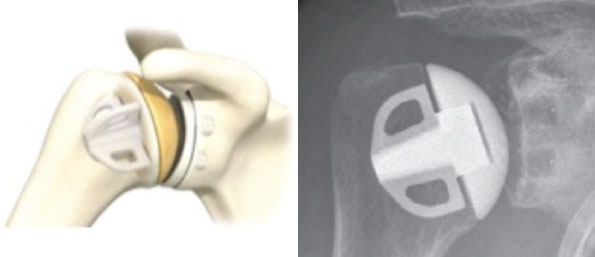

Affinis short (Mathys) links und postoperativesRöntgenbild (rechts), mit freundlicher Genehmigung der Fa. Mathys / Enovis

Falls dies nicht der Fall ist, wird eine Stielprothese gewählt, die in den Schaft des Oberarmknochens eingeschoben wird. Wenn auch der Knorpel der Gelenkpfanne abgenutzt ist, wird die Oberfläche der Pfanne ebenfalls ersetzt.

Man spricht dann von einer Schultertotalendoprothese.

Beispiel einer Schultertotalendoprothese (Affinis, Mathys,Enovis)